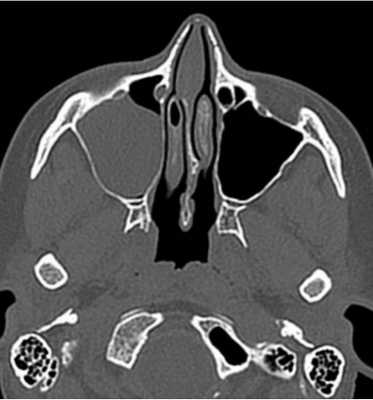

Этмоидит. МРТ придаточных пазух носа. Поперечная плоскость (увеличение), Т1-зависимое МРТ изображение.